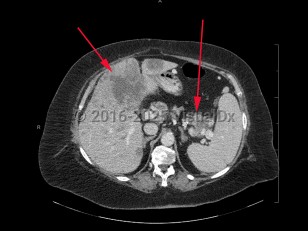

Metastatic pancreatic carcinomaMetastatic pancreatic carcinoma

Polycystic kidney diseasePolycystic kidney disease

Abdominal aortic aneurysmAbdominal aortic aneurysm